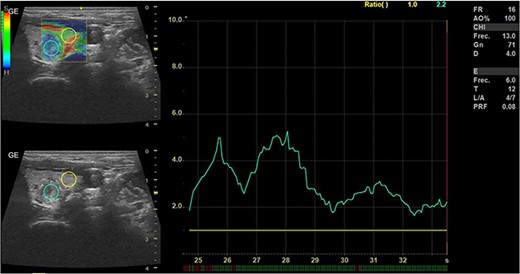

In May 2022, a thyroid ultrasound revealed a solid isoechoic left lobe TN measuring 12 × 11 × 13 mm, characterized by microcalcifications and irregular borders (Fig. 1). The color-flow Doppler ultrasound indicated increased perfusion, leading to its classification as a TI-RADS 5 nodule (Fig. 2). Elastography yielded a value of 2.2 (Fig. 3). Fine-needle aspiration confirmed Bethesda VI, consistent with thyroid papillary carcinoma.

Thyroid ultrasound: elastography, Left lobe and nodule. Pre-RFA procedure.